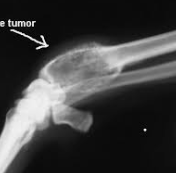

悪性骨腫瘍のなかで、家畜に多発するものは骨肉腫(osteosarcoma)です。

これには、造骨性骨肉腫(osteoplastic osteosarcoma)と軟骨肉腫(chondrosarcoma)があります。

骨肉腫は壮老齢の犬、とくに大型犬の四肢の長骨・肋骨に発しやすく、通常悪性度が高く、しばしば肺に転移し、動物は悪液質に陥って斃死するものが多い。

また上下顎、頭骨、骨盤、乳房にも発生します。馬では頭部に発生することがあります。